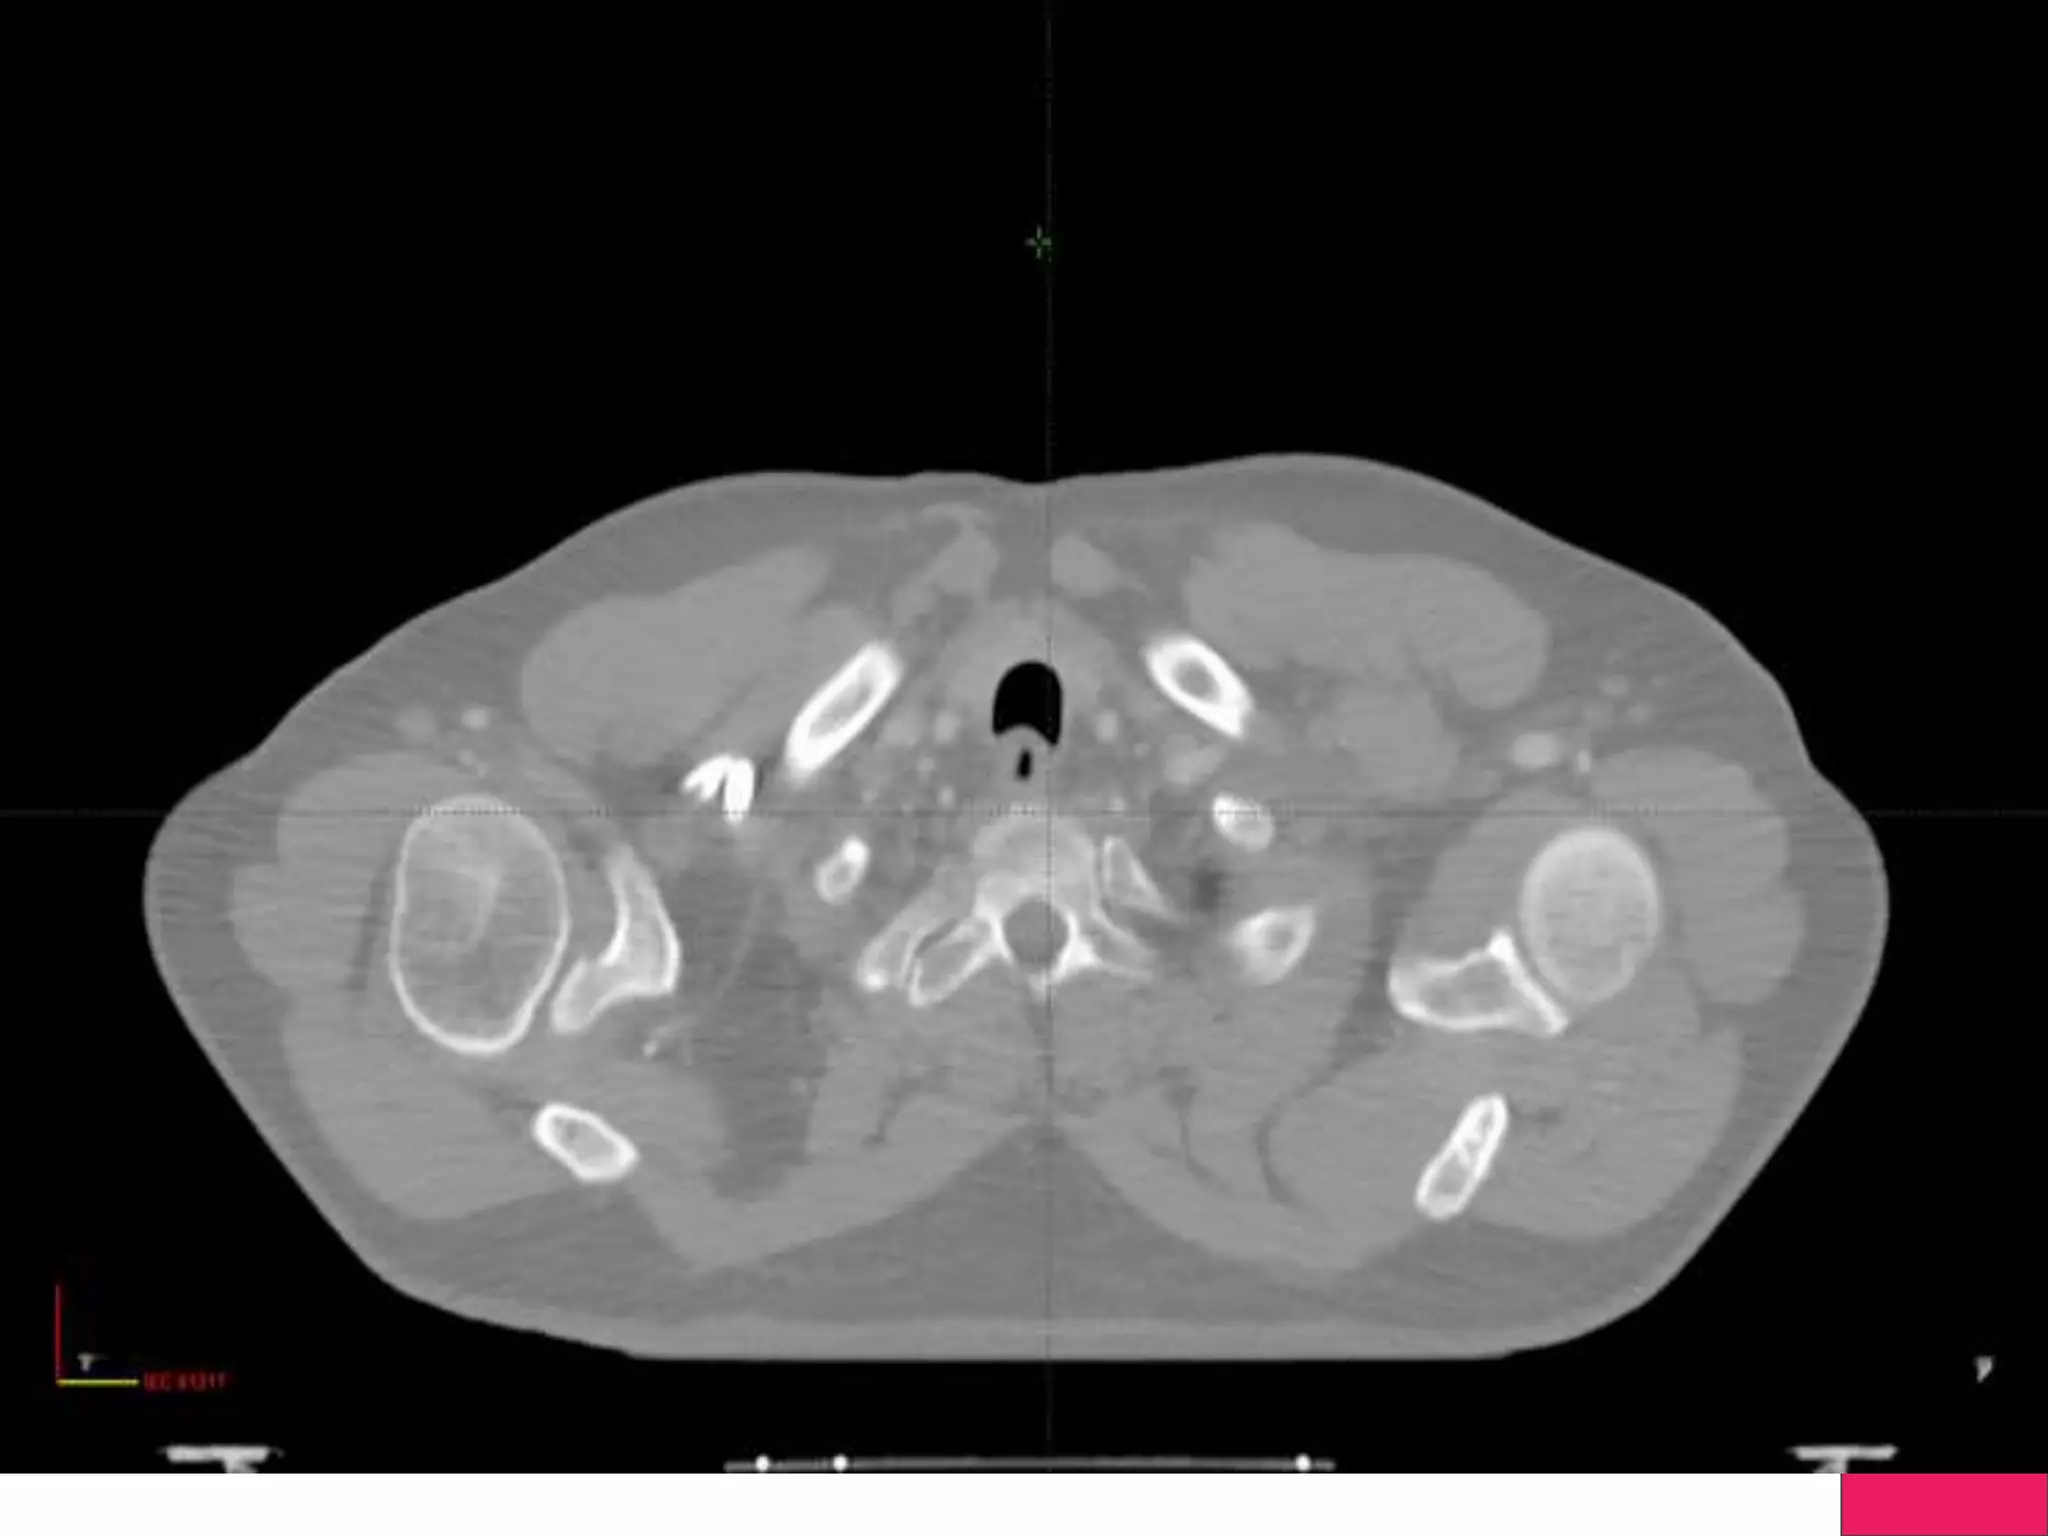

IGRT

Image Guided Radiotherapy, will use either 2D(Xray) or 3D

imaging (Cone Beam CT)

Linear Accelerators will have capability of doing a Xray and CT

Recent Development is Linac with MRI- !

Ensure the Efficiency of Treatment with the help of Imaging

Change in Anatomy can be found during treatment and corrected

IGRT Image Guided Radiotherapy,will use either 2D(Xray) or 3D imaging (Cone Beam CT) Linear Accelerators will have capability of doing a Xray and CT Recent Development is Linac with MRI- ! Ensure the Efficiency of Treatment with the help of Imaging Change in Anatomy can be found during treatment and corrected